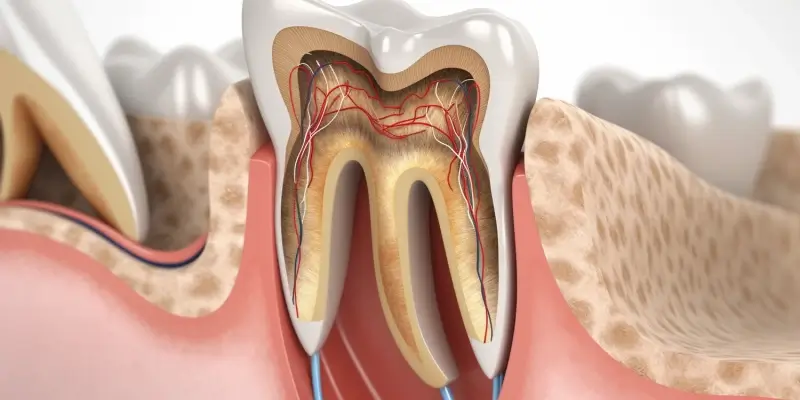

Jedną z podstawowych dziedzin jest **stomatologia zachowawcza**, która zajmuje się profilaktyką i leczeniem próchnicy oraz jej powikłań. Obejmuje ona wypełnianie ubytków, leczenie kanałowe (endodoncję) – czyli leczenie chorób miazgi zęba – oraz rekonstrukcję zniszczonych tkanek zęba. Stomatologia zachowawcza jest fundamentem zdrowia jamy ustnej, zapobiegając dalszemu niszczeniu zębów.

Leczenie próchnicy to kolejna fundamentalna usługa. Stomatolog diagnozuje ubytki próchnicowe i usuwa zainfekowane tkanki zęba, a następnie wypełnia ubytek odpowiednim materiałem, np. kompozytem. W przypadku głębokich ubytków, które dotarły do miazgi zęba, konieczne może być leczenie kanałowe (endodoncja), które polega na usunięciu miazgi, dezynfekcji kanałów korzeniowych i ich szczelnym wypełnieniu.